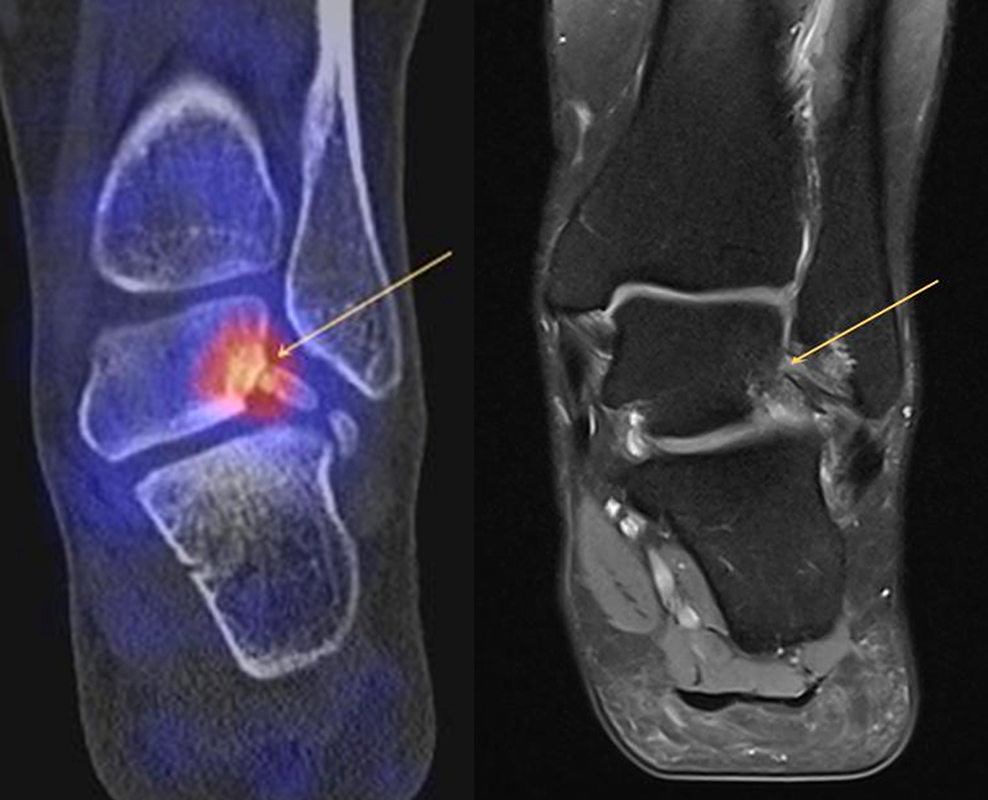

In Abbildung 3.4. ist ein typisches Beispiel für ein symptomatisches Os trigonum dargestellt.

Zum Lesen der Bildbeschreibung und zur Vollansicht bitte das Bild anklicken. Bild: H. C. Rischke

Bei der Differenzialdiagnose von Impingement-Syndromen am Sprunggelenk kann das SPECT/CT den Ort der Symptome- verursachenden Stressreaktion darstellen 32. Eine typische Ursache für ein posteriores Impingement kann ein Os trigonum sein. Scherkräfte im Bereich der Synchondrose eines Os trigonum lösen hypermetabole Stressreaktionen aus. Die Exzision des Os trigonum stellt eine erfolgreiche Therapie dar, sodass der Befund eines szintigraphisch aktivierten Os trigonum den Erfolg einer chirurgischen Therapie vorhersagen kann 3334.